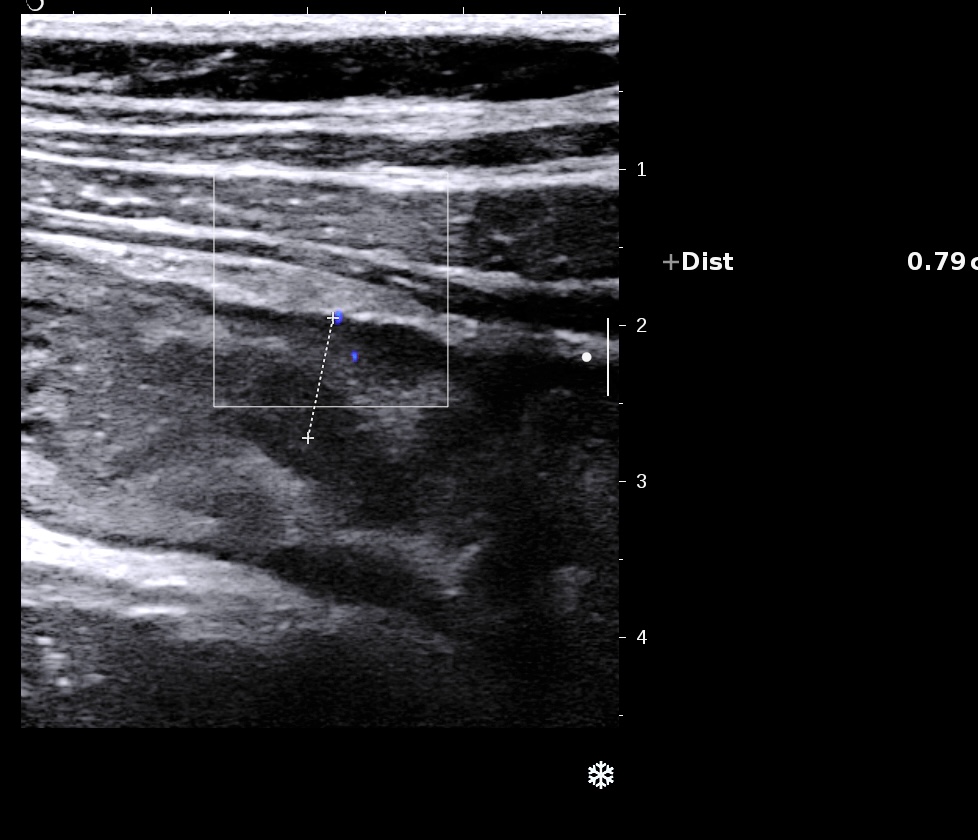

Le doppler est souvent limité à la paroi (Limberg 1 et 2), la graisse peu ou pas infiltrée

Les ganglions sont de petite taille

Malgré sa petite taille, ganglion rond, hypoéchogène donc inflammatoire

La graisse est peu infiltrée, l'activité doppler modérée.